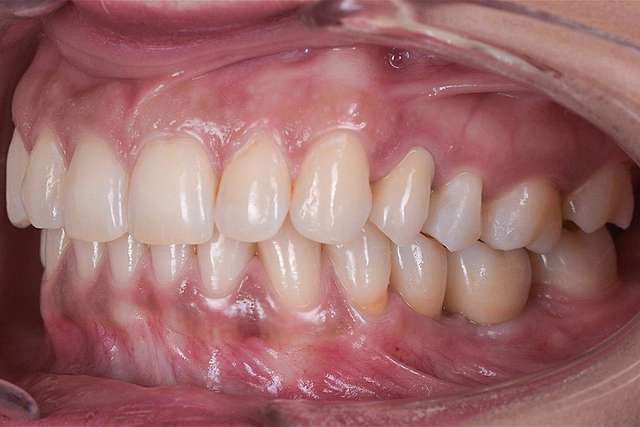

Chirurgia ghidata, ne faciliteaza o pozitie ideal pre-planificata, care nu tine cont doar de os, ci si de o pozitie optima in relatie cu viitorul dinte.Chirurgia ghidata înseamnă o precizie crescuta, care inseamna siguranta mai mare, timp operator mai scazut, si trauma mai mica. De asemenea focusul in acest tip de interventii a migrat spre reconstructia tesuturilor, care e pe termen lung are un impact mult mai mare atat estetic cat si biologic, inserarea implantului in sine fiind trivializata de folosirea ghidului chirurgical. Cazul de fata este un exemplu al acestui tip de abordare.